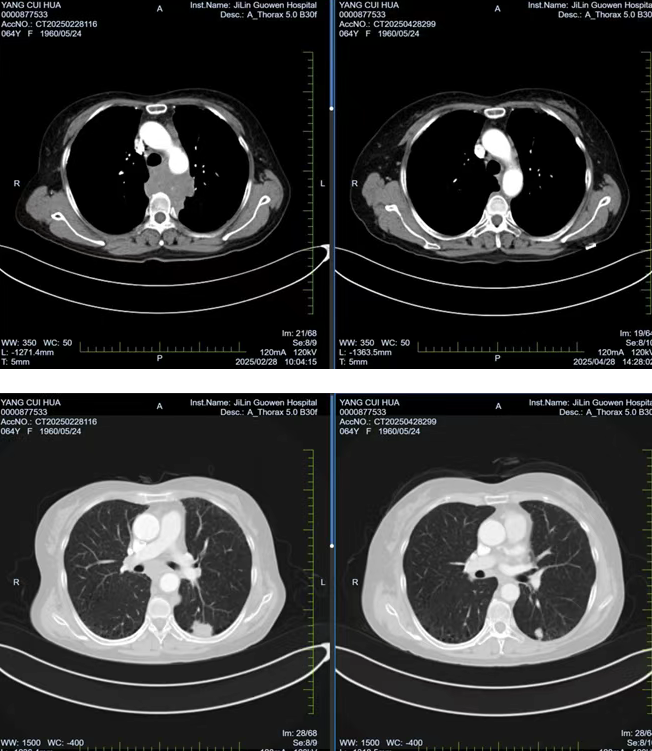

張阿姨因胸背部疼痛持續(xù) 1個(gè)月且逐漸加重,在當(dāng)?shù)蒯t(yī)院檢查時(shí)發(fā)現(xiàn)左肺存在腫物,初步考慮為惡性腫瘤。經(jīng)熟人介紹,了解到我院在腫瘤專科疾病治療方面的優(yōu)勢后,該患者前往我院就診。胸部腫瘤放化療二科為其安排了 PET/CT 檢查,并對(duì)左側(cè)鎖骨上腫大淋巴結(jié)進(jìn)行穿刺活檢,最終明確診斷為左肺下葉高級(jí)別神經(jīng)內(nèi)分泌癌,臨床分期為 cT1cN3M0 IIIb 期,且縱隔轉(zhuǎn)移淋巴結(jié)已侵犯椎體,患者因劇烈疼痛,生活質(zhì)量受到嚴(yán)重影響。